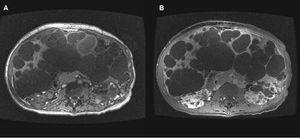

Figura 8. Resonancia magnética de una paciente mujer de 45 años de edad.